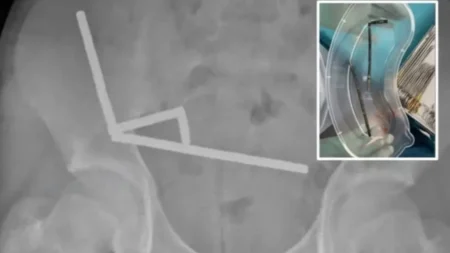

Një 13-vjeçar nga Zelanda e Re gëlltiti rreth 200 magnete, duke pësuar dëmtime serioze në zorrë. Ai pranoi se një…